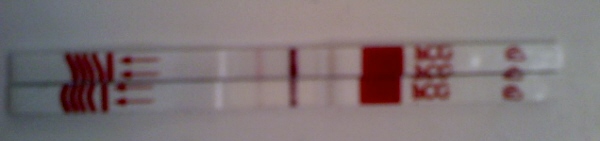

Gabi, a 12. hétig rizikós várni, de megértem, ha várni akarsz (és Pici, Te is).

Én a tavaszi vetélés után örültem, hogy a nyári szünetben lettem terhes, így amikor augusztusban mentem dolgozni (illetve táppénzre), már betöltöttem a 10. hetet, szóval már nem bántam, ha megtudják.

De az elején nagyon rossz lett volna...